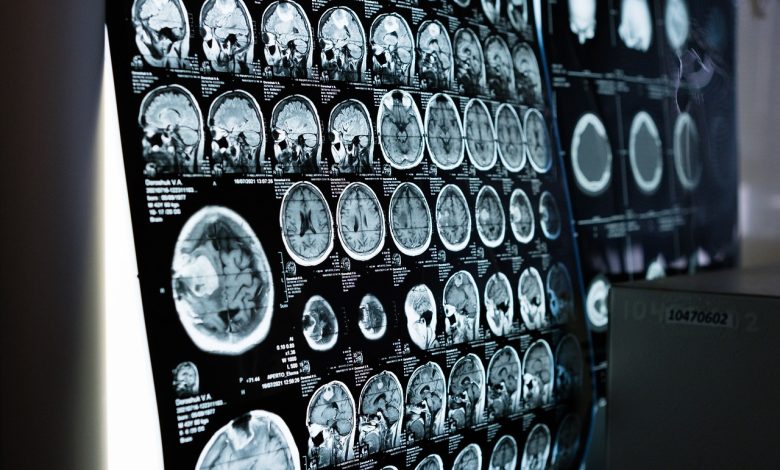

MONAI presenta framework para apps con IA de imágenes médicas

MONAI, un framework de IA de generación de imágenes médicas de código abierto, que se descargó más de 650 mil veces, está acelerado por NVIDIA y facilita la integración de estos modelos a los workflows clínicos con los paquetes de aplicaciones de MONAI, o MAP.

- Universidad de California, San Francisco: la UCSF está desarrollando MAP para varios modelos de IA, con aplicaciones que incluyen la detección de fracturas de cadera, la segmentación de tumores cerebrales y hepáticos, y la clasificación de cáncer de rodilla y mama.